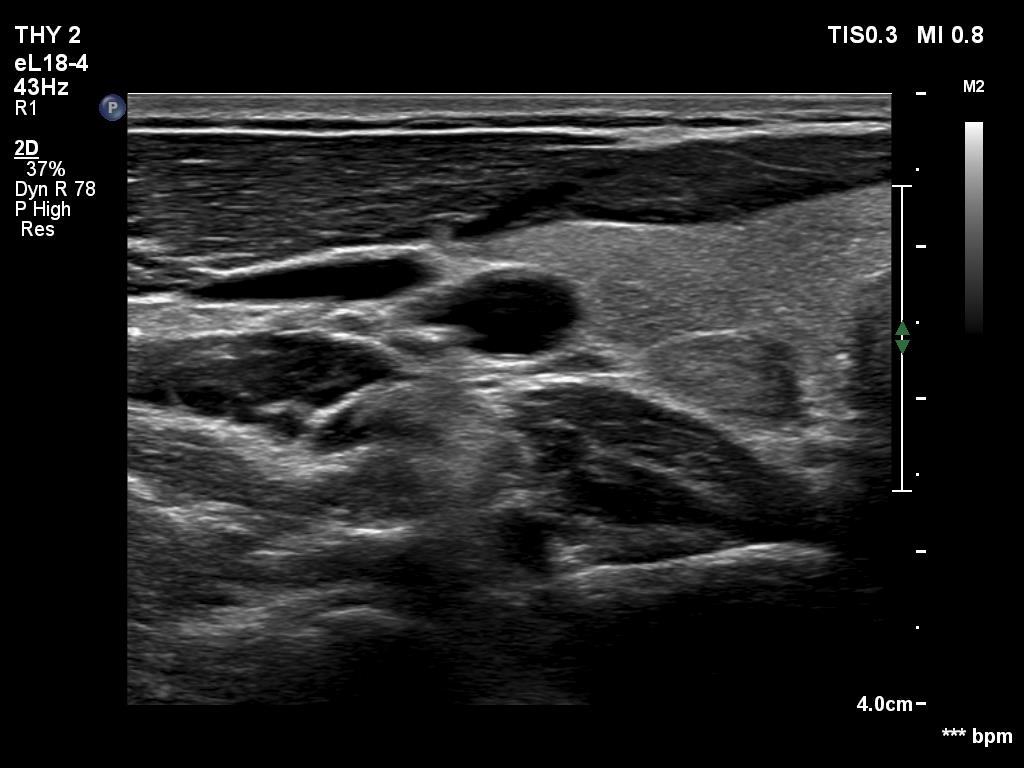

Ultrasonography. The thyroid was echonormal. There was a discrete, minimally hypoechoic area in the dorsal part of the right lobe. This was a technical artifact, caused by a connective tissue band crossing the thyroid. Although on transverse scan, the lesion looked deceptively as a discrete lesion, the real situation became clear on longitudinal scan.

The area in question did not correspond to a discrete lesion. It seemed to be circumscribed because of the presence of connective tissue running ventral which hindered the penetrance of ultrasound wave, therefore made the dorsal area hypoechoic.